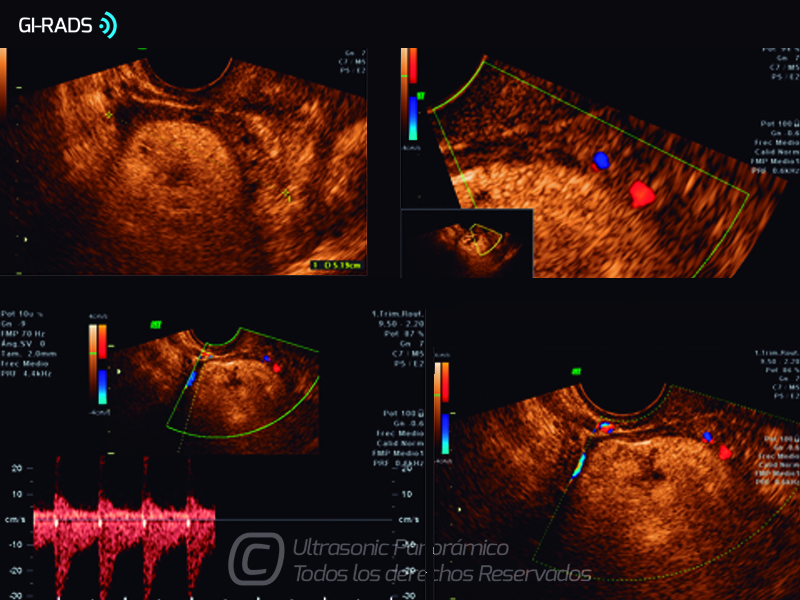

Patologías Benignas – Teratoma Maduro

• Patologías Benignas – Teratoma Maduro